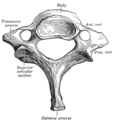

في البشر، الفقرات العنقية تكون أصغر من الفقرات الحقيقية، ويمكن تمييزها بسرعة عن الفقرات الصدرية أو القطنية حيث توجد الثقبة (فتحة) في كل نتوء مستعرض، والتي يمر من خلالها الشريان الفقري.

يكون جسم الفقرة العنقية أصغر من جسم الفقرة الصدرية، وذلك لأن الوزن الذي يتحمله أقل من الوزن الذي تتحمله الفقرة الصدرية. وشوكة الفقرة العنقية تكون أصغر ومشقوقة أيضاً. أما النتوء المستعرض ففيه ارتفاع أمامي وخلفي. في بعض البشر يكون هناك ضلع عنقي مرتبط بالفقرة العنقية السابعة وقد يسبب انسداد للشرايين والأوردة والأعصاب وكل الأعراض الناتجة من ذلك.